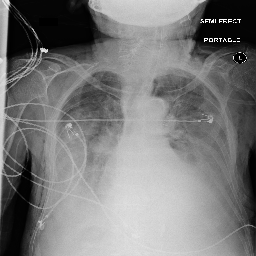

[Uncaptioned image] cardiomegaly is moderate. bibasilar atelectasis is mild. there is no pneumothorax. a lower cervical spinal fusion is partially visualized. healed right rib fractures are incidentally noted. ap portable upright view of the chest. there is no focal consolidation, effusion, or pneumothorax. the cardiomediastinal silhouette is normal. imaged osseous structures are intact. pa and lateral views of the chest. there is mild enlargement of the cardiac silhouette. there is no pleural effusion or pneumothorax. there is no acute osseous abnormalities.

[Uncaptioned image] as compared to the previous radiograph, the monitoring and support devices are unchanged. unchanged bilateral pleural effusions, with a tendency to increase, and resultant areas of atelectasis. the air collection in the bilateral soft tissues is slightly decreased. unchanged right picc line. no definite evidence of pneumothorax. as compared to the previous radiograph, the patient has received a nasogastric tube. the course of the tube is unremarkable, the tip of the tube projects over the middle parts of the stomach. there is no evidence of complication, notably no pneumothorax. the other monitoring and support devices are constant. constant appearance of the cardiac silhouette and of the lung parenchyma. as compared to the previous radiograph, there is no relevant change. tracheostomy tube is in place. there is a layering pleural effusions. NAME bilateral pleural effusion and compressive atelectasis at the right base. there is no pneumothorax.

[Uncaptioned image] the course of the dobbhoff feeding catheter is unremarkable, and its tip is seen projecting over the stomach. there is no evidence of complications, specifically no pneumothorax. as compared to the prior radiograph dated DATE, there has been no other significant interval change. ap portable upright view of the chest. overlying ekg leads are present. there is no focal consolidation, effusion, or pneumothorax. the cardiomediastinal silhouette is normal. imaged osseous structures are intact. as compared to the previous radiograph, there is no relevant change. the endotracheal tube terminates approximately 3 cm above the NAME. the endotracheal tube extends into the stomach. there is no evidence of complications, notably no pneumothorax. there is no pleural effusion or pneumothorax.

[Uncaptioned image] interval placement of a left basilar pigtail chest tube with improving aeration in the left mid to lower lung and near complete resolution of the pleural effusion. there are residual patchy opacities within the left mid and lower lung as well as at the right base favoring resolving atelectasis. no pneumothorax is appreciated on this semi upright study. heart remains stably enlarged. mediastinal contours are stably widened, although this NAME be related to portable technique and positioning. this can be better evaluated on followup imaging. no pulmonary edema. as compared to the previous radiograph, the patient has been extubated. the nasogastric tube is in unchanged position. the lung volumes remain low. moderate cardiomegaly with minimal fluid overload but no overt pulmonary edema. no larger pleural effusions. no pneumonia. ap upright and lateral views of the chest. there is moderate cardiomegaly. there is no pleural effusion or pneumothorax. there is no acute osseous abnormalities.

Table 4: Sample images along with ground truth and generated reports. Note that upper case tokens are results of anonymization.

Table 4 demonstrates the qualitative results of our full model. In general, our models are able to generate descriptions that align with the logical flow of reports written by radiologists, which start from general information (such as views, previous comparison), positive, then negative findings, with the order of lung, heart, pleura, and others. TieNet also generates report descriptions with such logical flow but in slightly different orders. For the negative findings cases, both our model and TieNet do well on generating reasonable descriptions without significant errors. Regarding the cases with positive findings, TieNet and our full model both cannot identify all radiological findings. Our full model is able to identify the major finding in each demonstrated case. For example, cardiomegaly in the first case, pleural effusion, and atelectasis in the second case.

A formerly practicing clinician co-author reviewed a larger subset of our generated reports manually. They drew several conclusions. First, our full model tends to generate sentences related to pleural effusion, atelectasis, and cardiomegaly correctly—which is aligned with the clinical finding scores in Table 3. TieNet instead misses some positive findings in such cases. Second, there are significant issues in all generated reports, regardless of the source model, which include the description of supportive lines and tubes, as well as lung lesions. For example, TieNet is prone to generate nasogastric tube mentions while our model tends to mention tracheostomy or endotracheal tube, and yet both models have difficulty identifying some specific lines such as chest tube or PICC line. Similarly, both systems do not generate the sentence with positive lung parenchymal findings correctly.

From this (small) sample, we are unable to draw a conclusion whether our model or TieNet truly outperforms the other since both present with significant issues and each has strengths the other lacks. Critically, neither of them can describe the majority of the findings in the chest radiograph well, especially for positive cases, even if the quantitative metrics demonstrate the reasonable performance of the models. This illustrates that significant progress is still needed in this domain, perhaps building on the directions we explore here before these techniques could be deployed in a clinical environment.